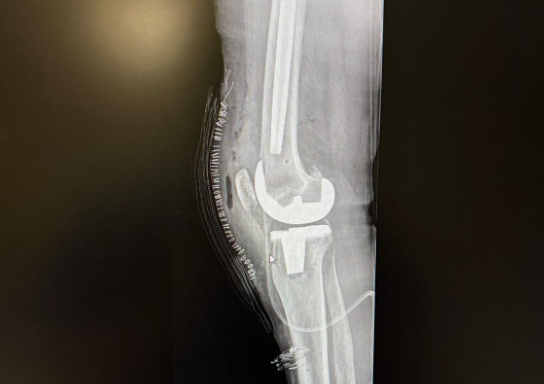

In late January this year, for various personal and medical reasons, not least being an existing, 40-year-old intramedullary femoral nail and a desire for not just surgery, but a full physical rehab program – I travelled to Valencia in Spain for a robotically assisted total knee replacement.